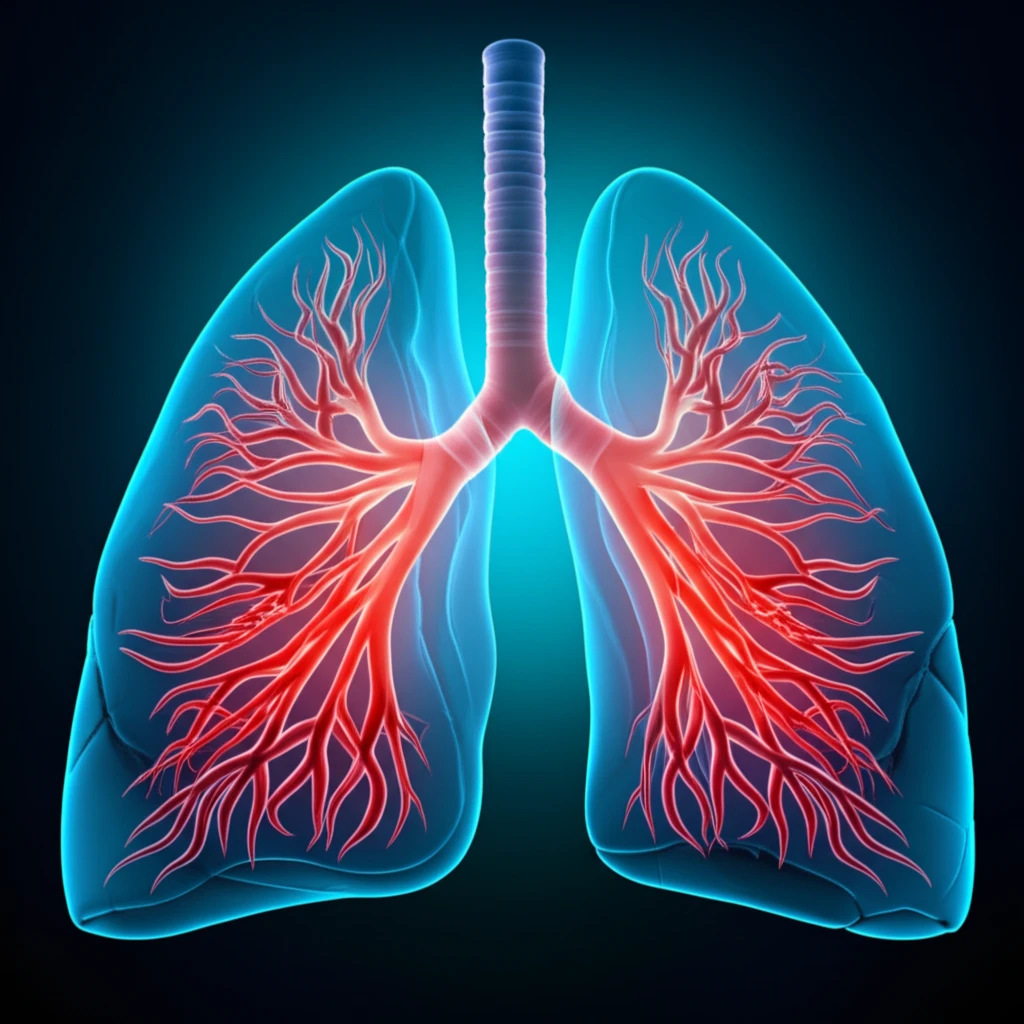

Angiogenesis, the process by which tumors develop new blood vessels, plays a crucial role in cancer progression. Understanding the unique vascular patterns within tumors can provide essential insights for effective treatment strategies. Recent advancements in CT perfusion (CTp) methodologies offer a non-invasive way to visualize and analyze these vascular patterns, providing high-resolution spatial and temporal data.

CT perfusion allows clinicians to measure key parameters, such as blood flow (BF), by tracking the movement of contrast agents through the tumor. Blood flow, in particular, has shown strong correlations with microvessel density (MVD), a biomarker for angiogenesis. By focusing on the initial passage of the contrast medium, CTp can minimize radiation exposure while providing critical diagnostic information.

Given the increasing interest in personalized medicine, understanding how blood flow differs between lung cancer subtypes is becoming increasingly important. This article explores how baseline blood flow characteristics vary between adenocarcinoma (AC) and squamous cell carcinoma (SCC), two major types of non-small cell lung cancer (NSCLC), and how these differences might impact treatment decisions.